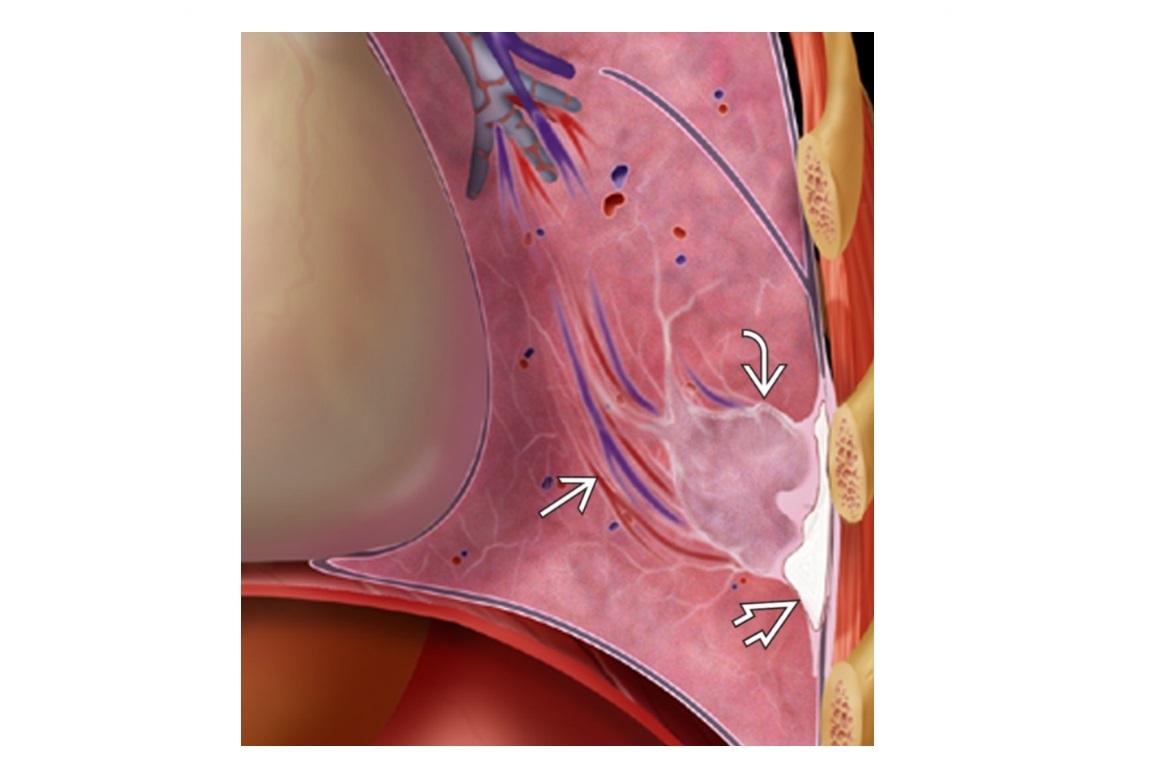

Angioinvasive aspergillosis

Halo sign

=Nodule/mass/consolidation surrounded by ground-glass opacity related to hemorrhage

Air crescent sign

=Crescent-shaped gas collection within nodule, mass, or consolidation

heralds improvement in the condition.